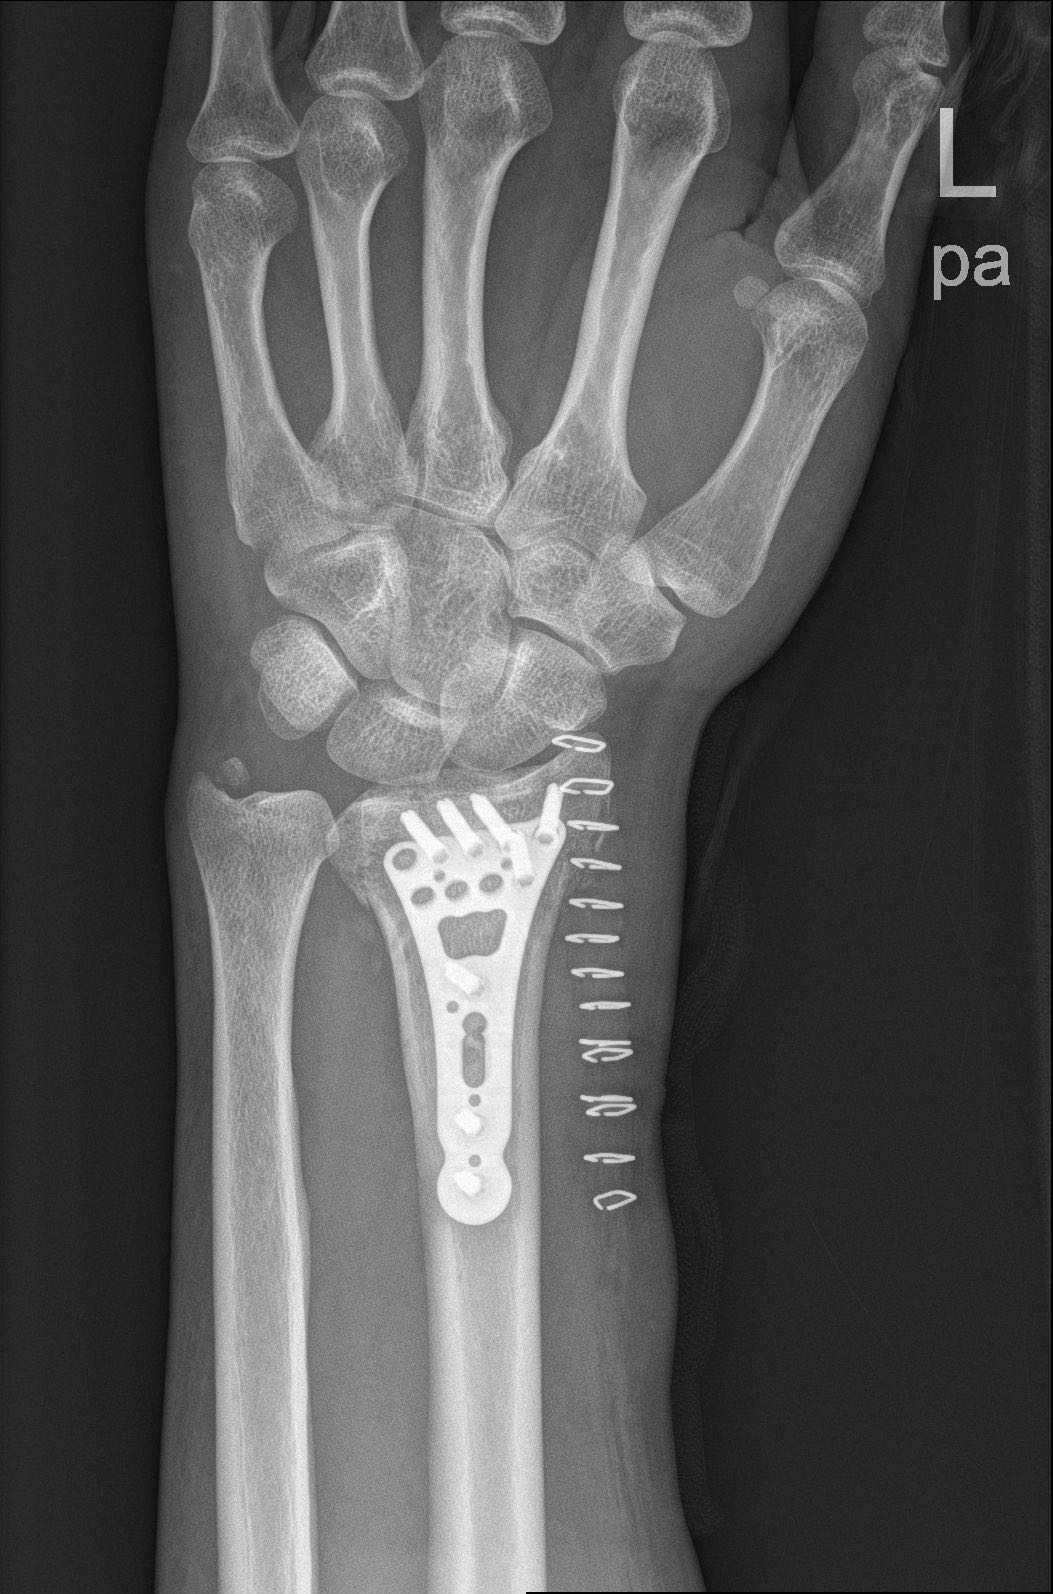

- 左手脱臼

园区老板殴打我,并一脚踩断我的左胫骨,打了10几分钟,随后把我丢在保安室。

我在里面痛了 8–9 小时才被人接出,然后送去医院,一直没交钱,医院就停药了,期间刘*坤怕我从医院跑,还偷偷把我身份证及所有证件哪些拿走,后面找他们要证件回国治疗不同意,自己想办法雇了壹*集团的护卫偷偷把我从医院接出去了,导致20多天没有及时治疗,这个事情不会这么结束的,证据我一大堆,有本事回国!